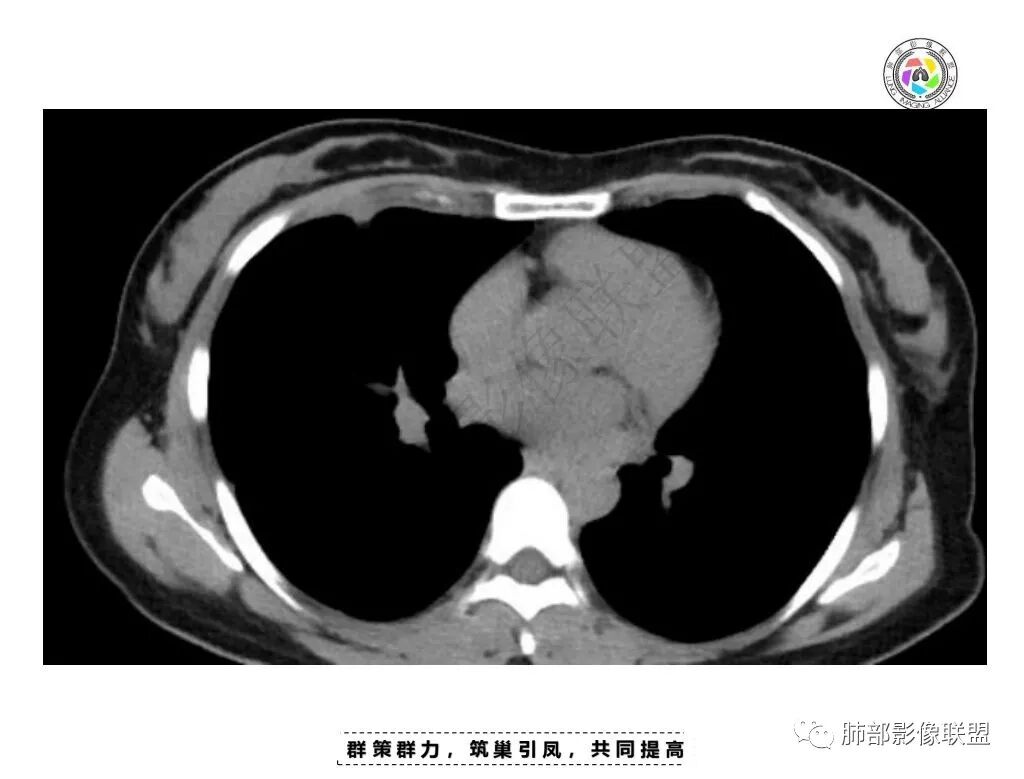

一月后复查,肺内病灶密度增高,边缘收缩,体积缩小,提示渗出朝增生转变;胸膜病灶缩小。

1.胸膜多发结节,边缘比较光滑,累及胸壁(胸痛也符合,一年),表现为脂肪间隙密度增高,最大的病灶累及肺内,附近有渗出,但是无放射状表现,增强中央有坏死灶,一月后似有缩小,肋骨完整未见破坏,支持炎性可能大!